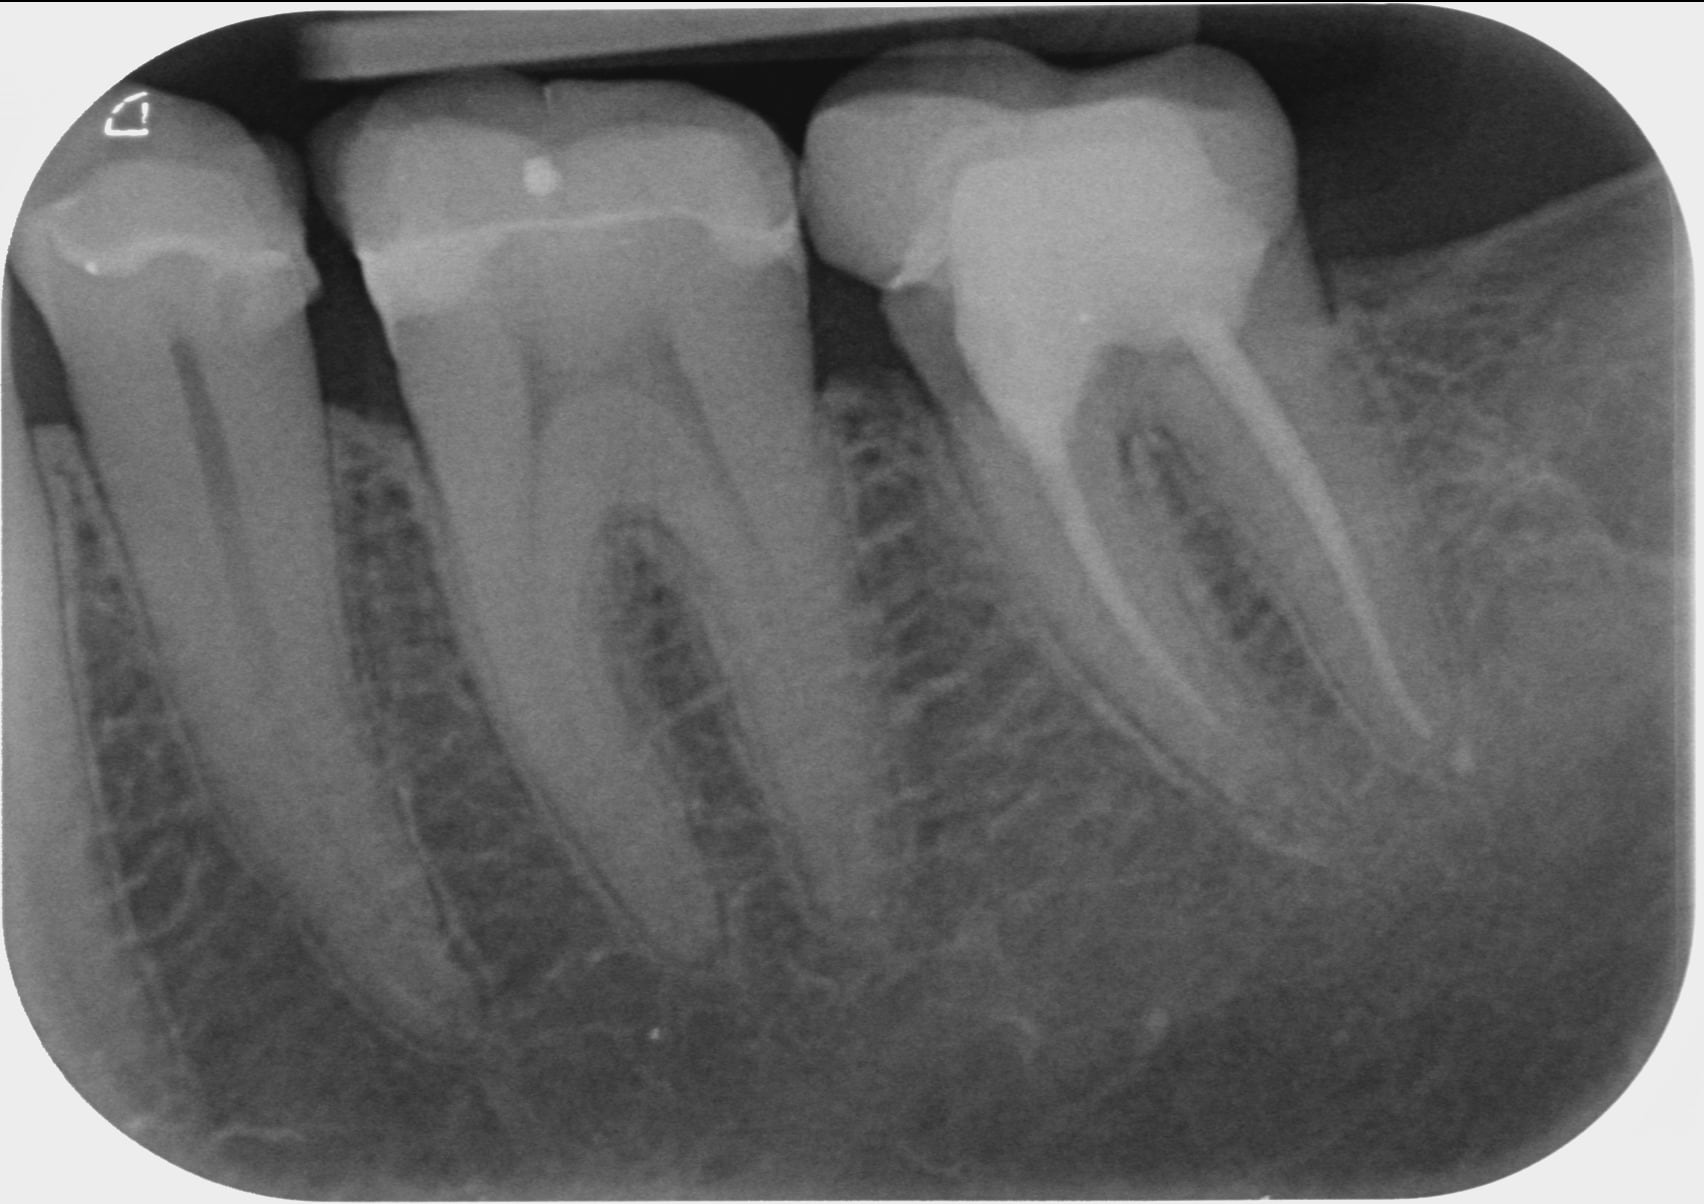

En PJ la rétro de la zone prise en 2016, 2018 et il y a un mois

elle dit : " PJ la rétro de la zone prise en 2016, 2018 et il y a un mois "

tu y vois une perte d os en 3 ans , toi ? moi non .

La couronne de 37 a un profil d'émergence mésial en surcontour

On pourrait comparer si la taille de la chambre pulpaire est diminuée sur 36 par rapport à 46. Signe d’une « souffrance » de type occlusale ou fêlure...

L expression paro existe entre la 6 et la 7 l os cortical disparait au sommet du septum.

A mon avis c est occluso chez une bruxomane nocturne + syndrome du septum (radio + douleur aliment filandreux)